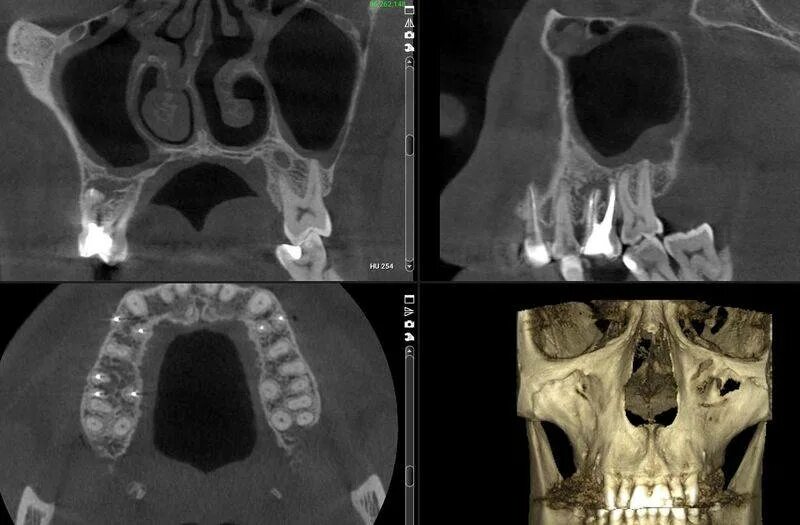

Синусит на кт